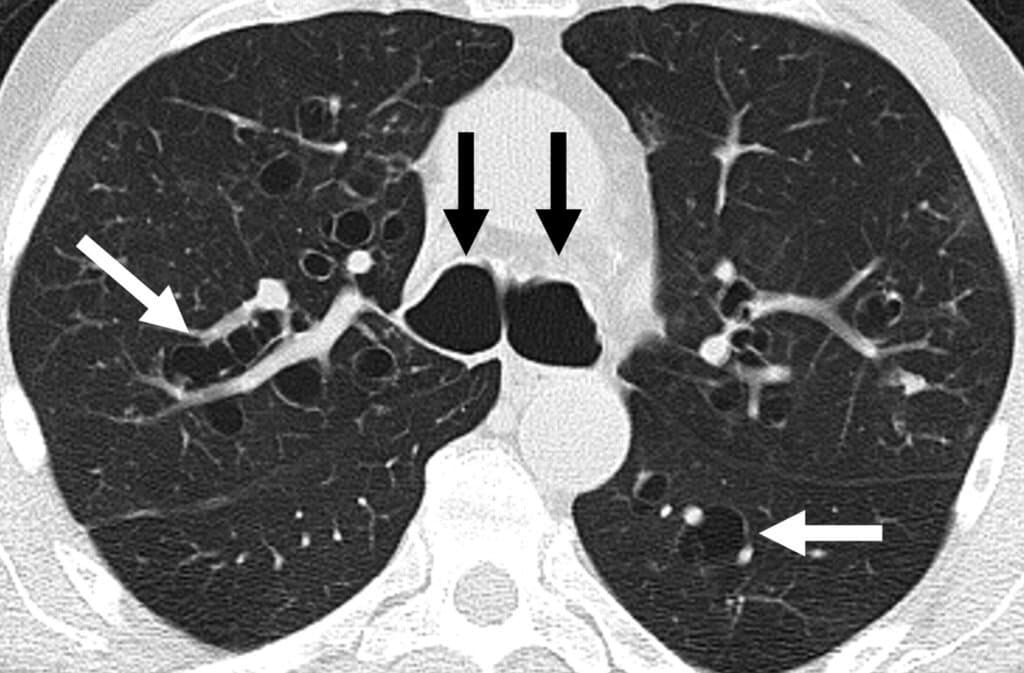

Das CT der ABPA-Patientin zeigte zentrale Bronchiektasen.

Die Untersuchung der 61-jährigen Frau ergab ein FEV1 von 65%, ein Gesamt-IgE von 496 IU/ml und eine Eosinophilie mit 1.340 Zellen pro Mikroliter. In der Thorax-CT zeigten sich zentrale Bronchiektasen. Spezifisches IgE und Hauttest waren positiv für Aspergillus, woraufhin die Ärzte eine allergische bronchopulmonale Aspergillose diagnostizierten.

Ihre nicht mit einem Biologikum behandelte Schwester benötigt hingegen weiterhin Steroide. Die CT zeigt zylindrische Bronchiektasen und multiple Areale mit mukoider Impaktion. Ausserdem fällt als Folge der Inflammation im Bereich der kleinen Atemwege ein Baumknospen-Zeichen auf (Tree-in-Bud-Muster).